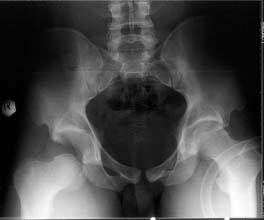

22 yrs man , semiprofessional( he earn some money from playing) basketball player got suffered in car accident.He had hip joint posterior luxation ( Pipkin 4) with little acetabular roof fragments ( nondisplaced) and anterosuperior abruption fracture of the head of the femur.

Additional injuries were severe face wounds. Emergency manipulations were reposition of the hip luxation under the radiologic control and wounds care. After reposition the CT scan was made. We found 2x3cm wide and 0.5 thick OCH fragment outside the joint surfaces , under the caput. The traction was applied.

i'd like to see post reduction x-rays to assess congruency of the reduction including AP & both Judet views. If the fragment is truly small, and extra-articular and the joint is stable, probably nothing needs to be done with the fragment, but i'd like more views! thanks

Here are the missing postreduction views.